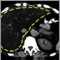

Es la inflamación del hígado más allá de su tamaño normal.

Si tanto el hígado como el bazo están agrandados, esto se denomina hepatoesplenomegalia.

El borde inferior del hígado normalmente llega justo hasta el borde inferior de las costillas (margen costal) sobre el lado derecho. El borde del hígado normalmente es delgado y firme y no puede sentirse con las puntas de los dedos por debajo del borde de las costillas, excepto al tomar una respiración profunda. Se puede considerar que está agrandado si el médico lo puede sentir en esta área.